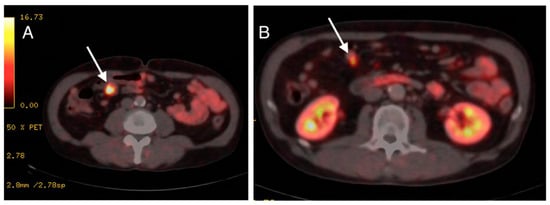

2. Case Presentation